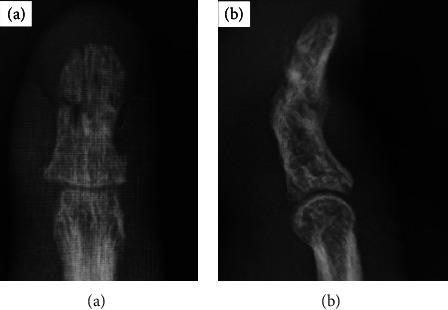

The nonunion of distal phalangeal communized fracture is relatively rare in hand fractures. However, if it occurred, the surgical treatment is quite difficult because of small piece of fragmentations. We developed a new fixation method that involves the insertion of two wires and external wire compression fixation using a metal clamp. The aim of this technique was to increase the compression force between fragments and rigidity of conventional percutaneous Kirschner wire fixation. Here, we present a patient with the nonunion of distal phalangeal communized fracture who was satisfactorily treated with open reduction and percutaneous interfragmentary compression fixation with a linking external wire fixator (the Ichi-Fixator system). Such a treatment that enables compression fixation for communized distal phalangeal fracture of nonunion will clearly boost bone healing. Linked external wire-type compression fixator (the Ichi-Fixator system) enables enhanced security of fixation and facilitates the bone healing.

指骨远端粉碎性骨折不愈合在手部骨折中相对少见。然而,如果发生这种情况,由于骨折碎片较小,手术治疗相当困难。我们开发了一种新的固定方法,即插入两根钢丝并使用金属夹进行外部钢丝加压固定。该技术的目的是增加骨折碎片之间的压缩力以及传统经皮克氏针固定的刚度。在此,我们报告一例指骨远端粉碎性骨折不愈合患者,采用切开复位并用连接外部钢丝固定器(Ichi固定器系统)进行经皮骨折块间加压固定,治疗效果满意。这种能够对不愈合的指骨远端粉碎性骨折进行加压固定的治疗方法将显著促进骨愈合。连接外部钢丝式加压固定器(Ichi固定器系统)可提高固定的安全性并促进骨愈合。